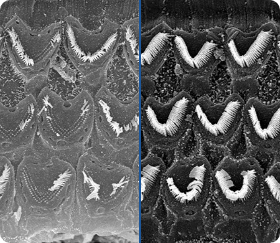

Mit den Fortschritten in Wissenschaft und Technik stellen sich die Forscher immer wieder die Frage, ob es möglich ist, ein Präparat herzustellen, das in der Lage ist, das Gewebe des Trommelfells und die Haarzellen der Cochlea zu erneuern. Denn die Zerstörung der Haarzellen führt zu einem teilweisen oder vollständigen Verlust des Hörvermögens - und ihre Wiederherstellung hat den Effekt, dass sich das Hörvermögen verbessert und die Schallwahrnehmung verbessert. Könnte die innovative Formulierung von AudioVerde eine Chance bieten, die Zellen auf natürliche Weise wiederherzustellen und das Hörvermögen von Menschen mit Hörminderung zu verbessern?

Haarzellen bei Hörstörungen und nach der Hörverbesserung. / Bewegen Sie den Schieberegler, um den Unterschied zu sehen.